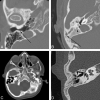

A variety of congenital syndromes affecting the face occur due to defects involving the first and second BAs. Radiographic evaluation of craniofacial deformities is necessary to define aberrant anatomy, plan surgical procedures, and evaluate the effects of craniofacial growth and surgical reconstructions. High-resolution CT has proved vital in determining the nature and extent of these syndromes. The radiologic evaluation of syndromes of the first and second BAs should begin first by studying a series of isolated defects: CL with or without CP, micrognathia, and EAC atresia, which compose the major features of these syndromes and allow more specific diagnosis. After discussion of these defects and the associated embryology, we proceed to discuss the VCFS, PRS, ACS, TCS, Stickler syndrome, and HFM.